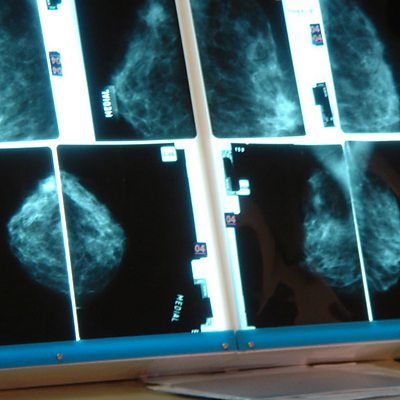

Prof Beral believes breast cancer could be cut significantly with a "hormonal vaccine".